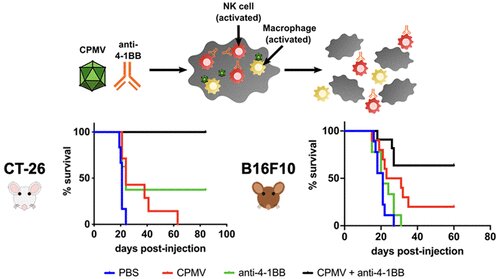

加州大学圣地亚哥分校的研究人员进行的一项研究显示,一种对抗癌症的新组合疗法可能由一种植物病毒和一种激活免疫系统的自然杀伤细胞的抗体组成。在结肠癌小鼠模型中,联合治疗消除了所有肿瘤,并阻止了它们的复发,进而获得了100%的生存率。该疗法还提高了黑色素瘤小鼠模型的存活率。